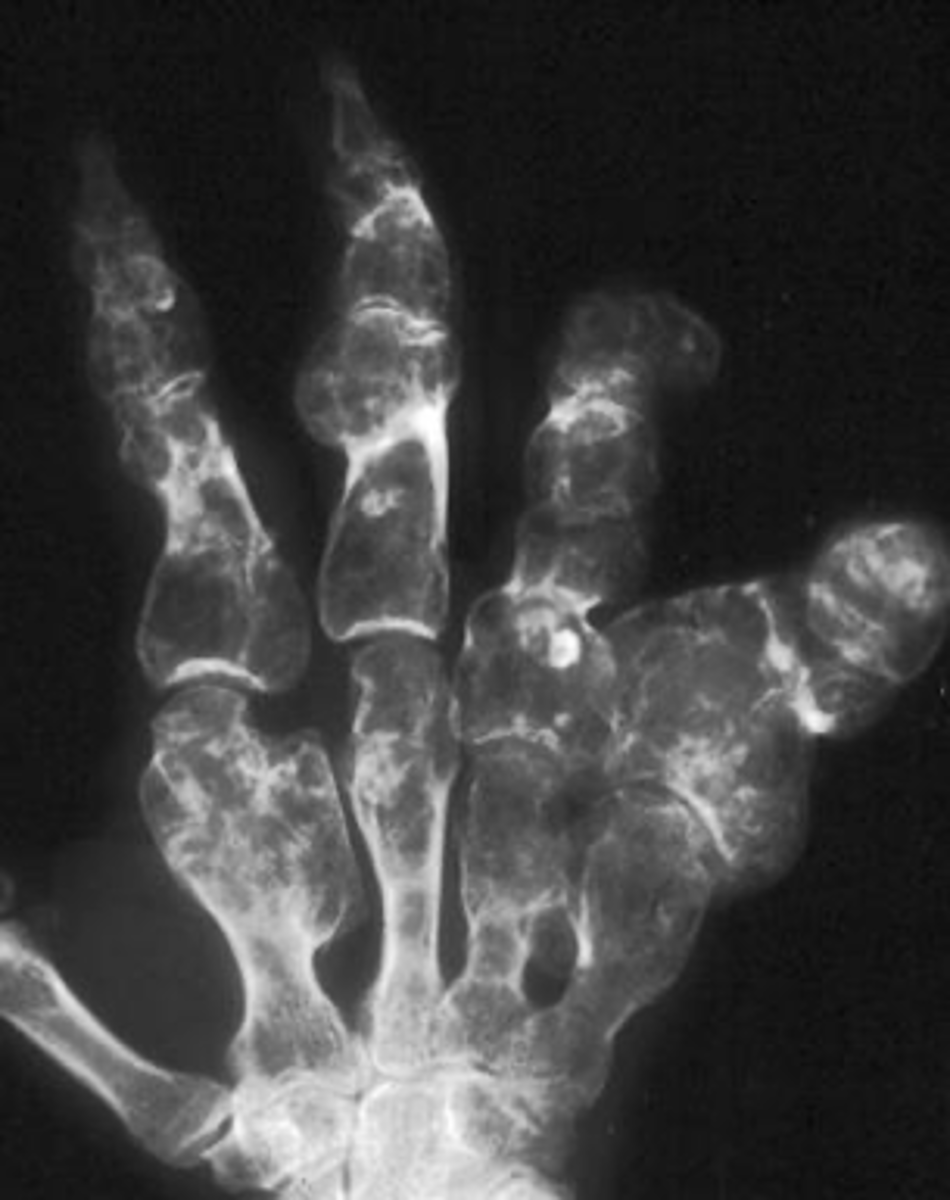

Multiple enchondromas

ID benign tumor